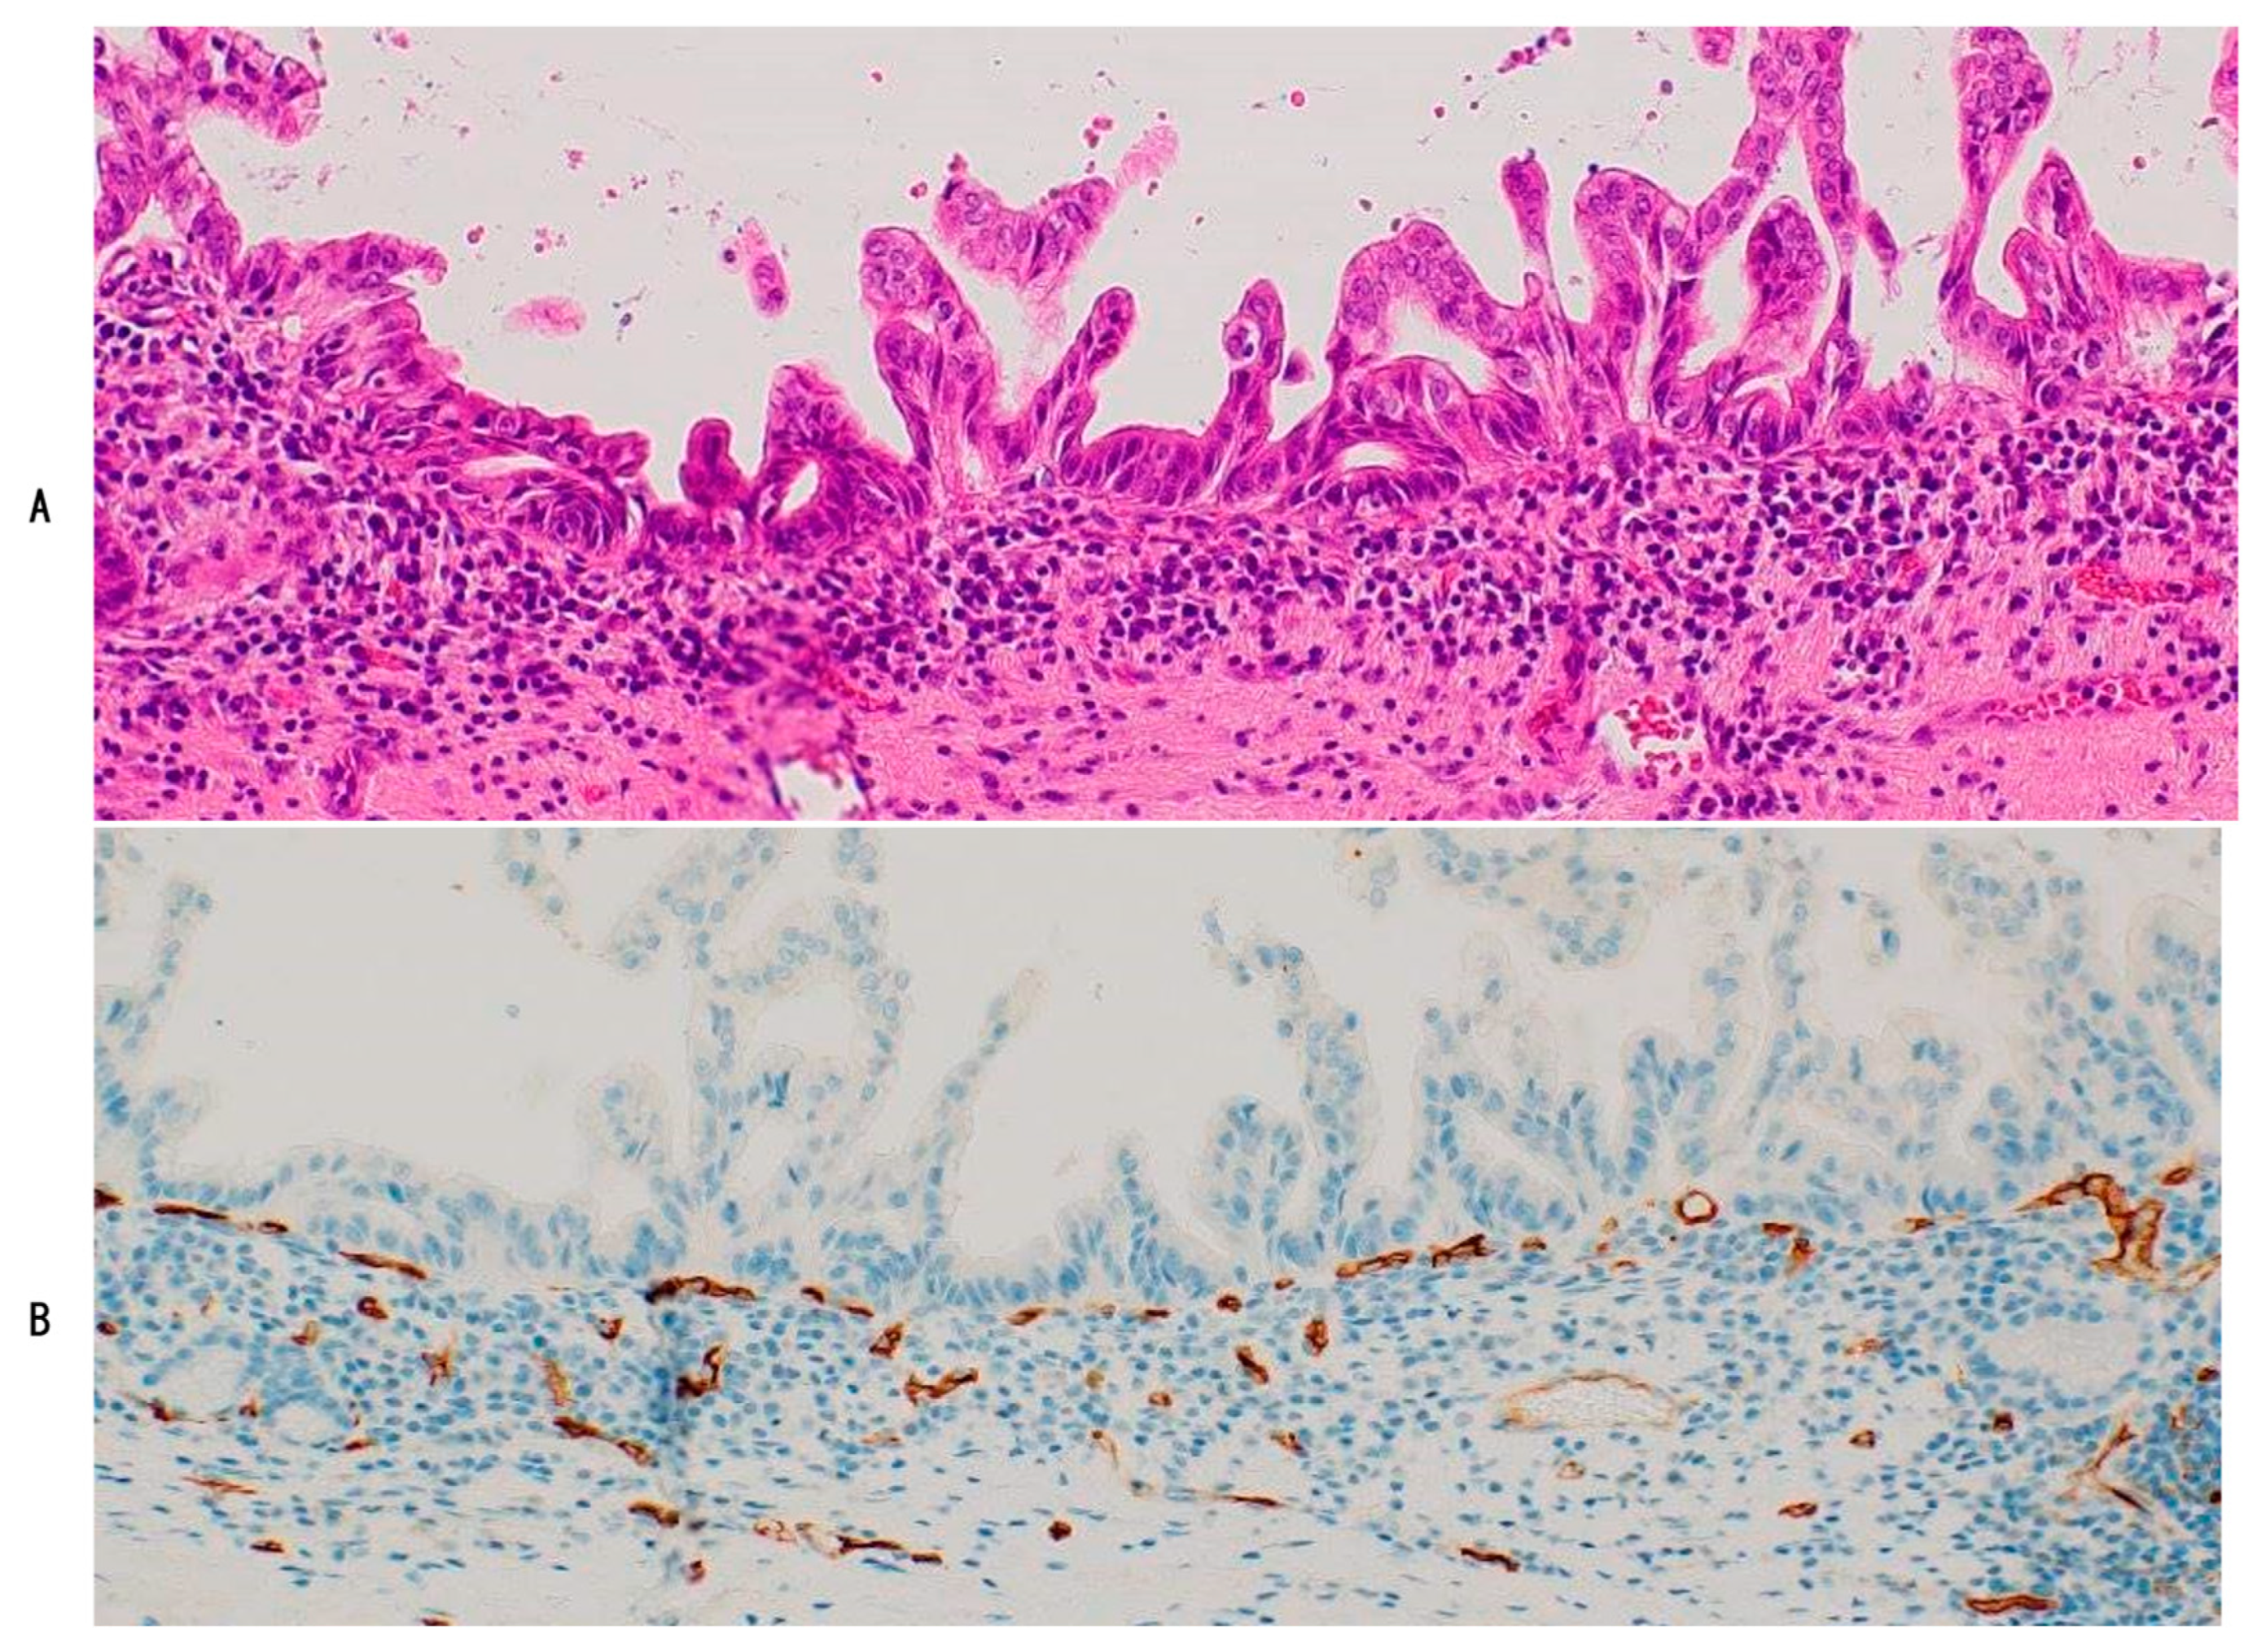

The epithelial lining of high-grade BilIN is always underlined by regular and dense dotted capillaries (PCP-like capillaries) (Table 3) (Figure 3) [11,12]. These PCP-like capillaries are continuous with PCP in the surrounding non-neoplastic biliary mucosa, suggesting that (i) the non-neoplastic epithelia of the bile duct and gallbladder were intraepithelially replaced by the neoplastic epithelia of high-grade BilIN, and (ii) pre-existing PCP of these non-neoplastic lining epithelia might have been hijacked and used as supplying vessels of high-grade BilIN (vessel co-option) [1,11,12]. High-grade BilIN seems to require a blood supply for growth, similar to non-neoplastic biliary epithelia. These processes resemble the regenerative process of biliary lining epithelia, which finally restores the biliary tract [11]. The mechanisms involved in the regeneration and replacement of biliary lining epithelia after injuries may also be involved in the replacement process of high-grade BilIN.

Figure 3.

Dotted chain-like capillaries resembling peribiliary capillary complex (PC) of normal bile ducts are located under neoplastic epithelia of high-grade biliary intraepithelial neoplasm (BilIN). (A), HE and (B), CD34 immunostaining.